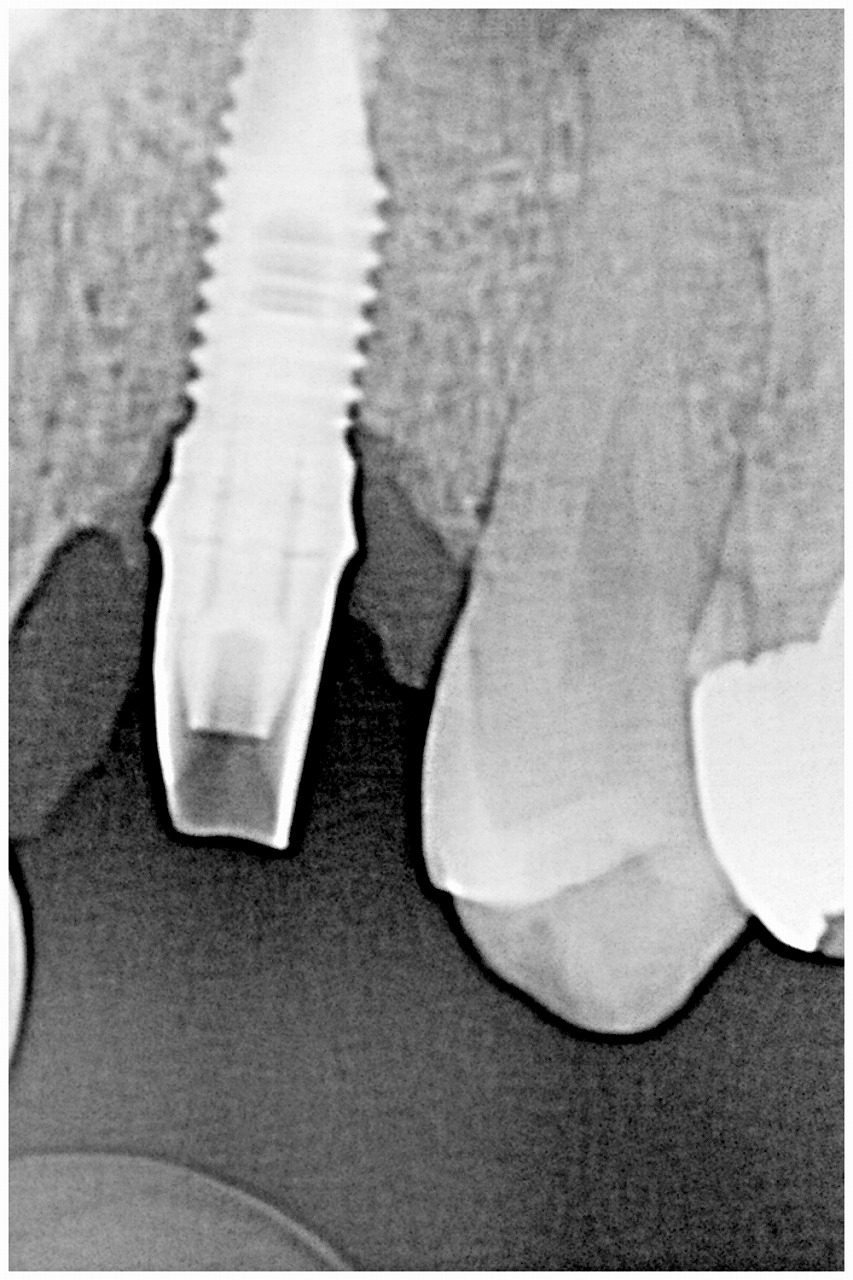

左上の4番部のインプラント部の上部構造を作成していきます|お知らせ |広島市安佐南区の歯科医院 左上の4番部のインプラント部の上部構造を作成していきます トップ お知らせ・ブログ お知らせ 左上の4番部のインプラント部の上部構造を作成していきます 左上の4番部のインプラント部の上部構造を作成していきます 術後のパノラマになります デンタルレントゲンになります これより歯肉形態を付与していきます 歯肉形態を付与していきました 綺麗な歯肉形態を作成していきました アバットメントを建てていきました ジルコニアクラウンが入りました 綺麗な歯が入りました Web診療予約 初めての方へ 選ばれ続ける理由 院内設備について 歯が痛いしみる一般歯科 歯がぐらぐらする歯周病 健康な歯を保ちたい予防歯科 子供の虫歯予防をしたい小児歯科 銀歯をセラミックに審美歯科 白い歯を目指しませんか?ホワイトニング 矯正専門医がいるので安心矯正歯科 抜けた歯を補いたいインプラント・入れ歯 医院案内 スタッフ紹介 メリィハウス歯科クリニックオフィシャルホームページ ラベンダー歯科クリニックオフィシャルホームページ お知らせ・ブログ ホーム 診療科目 一般歯科 歯周病治療 予防治療 小児歯科 審美治療 ホワイトニング 矯正歯科 入れ歯・インプラント マウスピース矯正 初めての方へ 院長・スタッフ 設備紹介 医院案内・アクセス メニューを閉じる